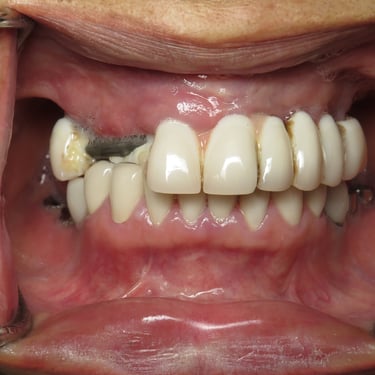

Pérdida de múltiples dientes

La pérdida de múltiples dientes es la ausencia de varios dientes que puede ser resultado de caries, enfermedades periodontales o traumatismos.

Los pacientes notan varios espacios vacíos en su boca, lo que afecta su capacidad para masticar y hablar adecuadamente.

El tratamiento incluye la colocación de varios implantes dentales para restaurar la función y la estética.